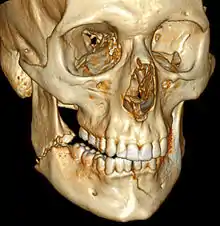

![]() | |

| 3D computed tomographic image of a mandible fracture in two places. One is a displaced right angle fracture and the other is a left parasymphyseal fracture. | |

Computed tomography is the most sensitive and specific of the imaging techniques. The facial bones can be visualized as slices through the skeletal in either the axial, coronal or sagittal planes. Images can be reconstructed into a 3-dimensional view, to give a better sense of the displacement of various fragments. 3D reconstruction, however, can mask smaller fractures owing to volume averaging, scatter artifact and surrounding structures simply blocking the view of underlying areas.

3D CT reconstruction of mandible fracture, white arrow marks fracture, red arrow marks moderate displacement and open bite